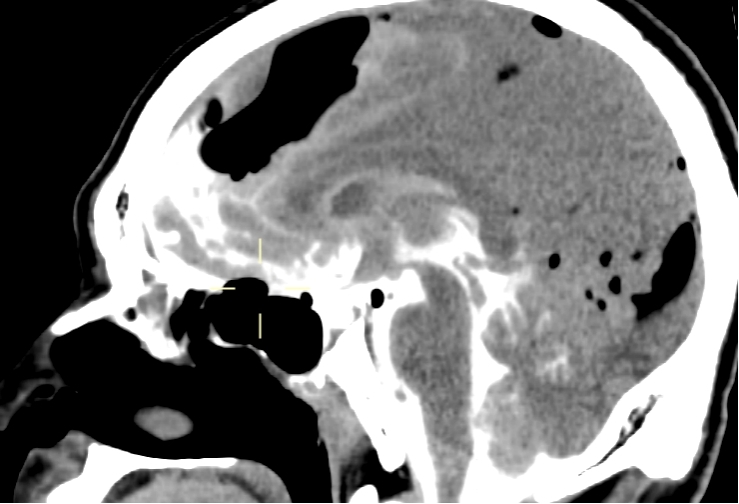

我院PET-CT检查显示鼻咽周围骨质改变,未见异常代谢增高,无肿瘤复发;左侧颞叶、左侧岛叶及左侧鞍旁片状低密度影,伴代谢稀疏,提示放射性坏死。脑室造影检查显示颅内积气,前颅底鞍结节颅骨缺损,脑脊液漏可能(图1-3)。MRI检查显示左侧颞叶内侧面不规则强化病灶,考虑放射性脑坏死改变(图4)。